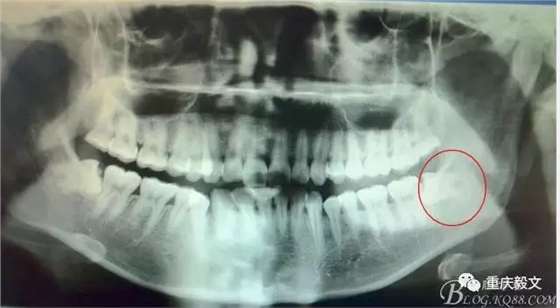

患者、李xx、女、20歲,主訴:左側(cè)下后牙牙齦不適數(shù)天。??茩z查:38水平位、牙冠萌出黃豆大小,頰側(cè)牙齦未見明顯紅腫,全景片檢查:38水平位、雙根、分叉大,37遠中頸部未見齲壞。診斷:38中位水平阻生 治療計劃:微創(chuàng)拔除38。術(shù)前與患者充分溝通,告訴患者采用無痛sta阻滯麻醉加不切開翻瓣拔除。患者同意手術(shù)方案,簽知情同意書。

圖1.全景片檢查:38水平位、雙根、分叉大。